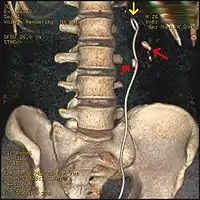

Hay otras causas poco frecuentes de la hematuria de origen renal, como la compresión de la vena renal izquierda (síndrome de cascanueces).[6] En este trastorno, con frecuencia una malformación benigna, la vena renal izquierda queda apretada entre la aorta abdominal y arteria mesentérica superior. Con un poco de imaginación, la aparición en la arteriografía de este síndrome suele recordar un cascanueces. El diagnóstico se sospecha con la ecografía renal y es confirmado por la venografia o Angio-Resonancia Magnética Nuclear abdominal. Ocasionalmente este síndrome se asocia con hematuria, dolor de espalda y, a veces, la proteinuria.

Dado que la hematuria puede ser intermitente, incluso un solo episodio documentado debe ser considerado significativo y debe dársele una evaluación completa.[10] La parte superior del tracto, que incluye el riñón y uréter, suelen ser evaluados con un pielograma intravenoso, la tomografía computarizada (TAC) o un pielograma retrógrado. La TAC se debe realizar con contraste intravenoso e incluyen tomas de imágenes una vez que el contraste ha llenado el sistema colector del tracto superior.[10] El tracto inferior, que incluye la vejiga y la uretra, suele ser evaluado por cistoscopia.

Tanto la ecografía y la urografía intravenosa orientan de forma casi inequívoca hacia la etiología del proceso que ha ocasionado la hematuria.[9] La tomografía está indicada en función de los resultados de la ecogafía y la urografía, siendo la modalidad preferida para la detección y caracterización de masas renales, cálculos e infecciones renales. En pacientes alérgicos al yodo o con fallo renal, se suele indicar una resonancia magnética. La biopsia renal se reserva cuando se sospecha una enfermedad del parénquima renal.[12] Por ejemplo, una biopsia del riñón se debe realizar cuando existe proteinuria grave o persistente asociada a la hematuria o una hematuria macroscópica durante más de tres semanas, un deterioro de la función renal, una sospecha de Lupus nefrítico o una hematuria macroscópica recurrente.